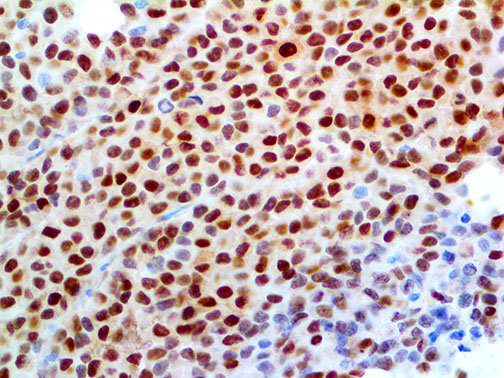

It is the ICU physician who is most likely to witness one of the deadliest manifestations of the abnormal immunological response, the cytokine storm syndrome (CSS). This response is also referred to by some as the cytokine release syndrome (CRS). CSS is characterized by continuous activation and expansion of macrophage and lymphocyte populations, which secrete large amounts of cytokines, causing the cytokine storm. This massive cytokine release is akin to hemophagocytic lymphohistiocytosis (HLH) disease, a syndrome characterized by initial unchecked and persistent activation of cytotoxic T lymphocytes and NK cells.

Clinical and laboratory manifestations of HLH include fever, enlarged liver and/or spleen, neurologic dysfunction, coagulopathy, liver dysfunction, cytopenias (i.e., low levels of erythrocytes, leukocytes, and/or platelets), hypertriglyceridemia, hyperferritinemia, hemophagocytosis, and eventually diminished NK cell activity as the immune system becomes progressively paralyzed. HLH can be familial (primary HLH) or secondary to another disease process (sHLH), such as rheumatic disease, in which it is referred to as macrophage activation syndrome (MAS, characterized by elevated ferritin).